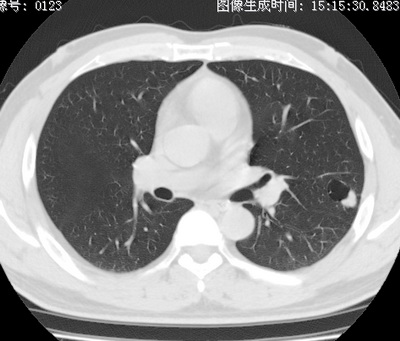

以下是引用zhao_bin2008在2010-1-4 20:15:00的发言:[br]先天性肺囊肿或小的肺隔离症?

以下是引用卜一在2010-1-4 22:09:00的发言:[br]先天性肺囊肿或小的肺隔离症?支持!

以下是引用zsl6918在2010-1-5 5:23:00的发言:[br]良性改变!肺囊肿,先天性支气管闭锁,血管畸形等均有可能。

以下是引用影像之路在2010-1-6 11:10:00的发言:[br]腺癌,最终的病检有些出乎意料之外,术前同志们大多考虑为肺囊肿或小的肺隔离征 [br]回过头来看 小结节呈分叶状,其内侧有一条较粗的静脉供血或许能成为支持诊断腺癌的理由